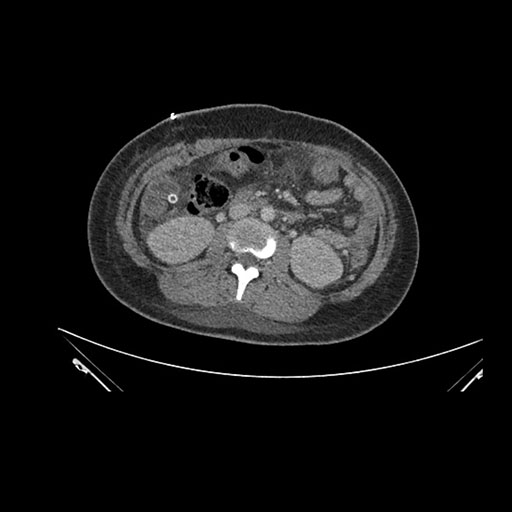

Imaging Analysis

Look through the patient's CT scan to identify any areas of concern for the necessary procedure.

Axial Venous

Based on initial findings, which issue(s) would you be most concerned about?